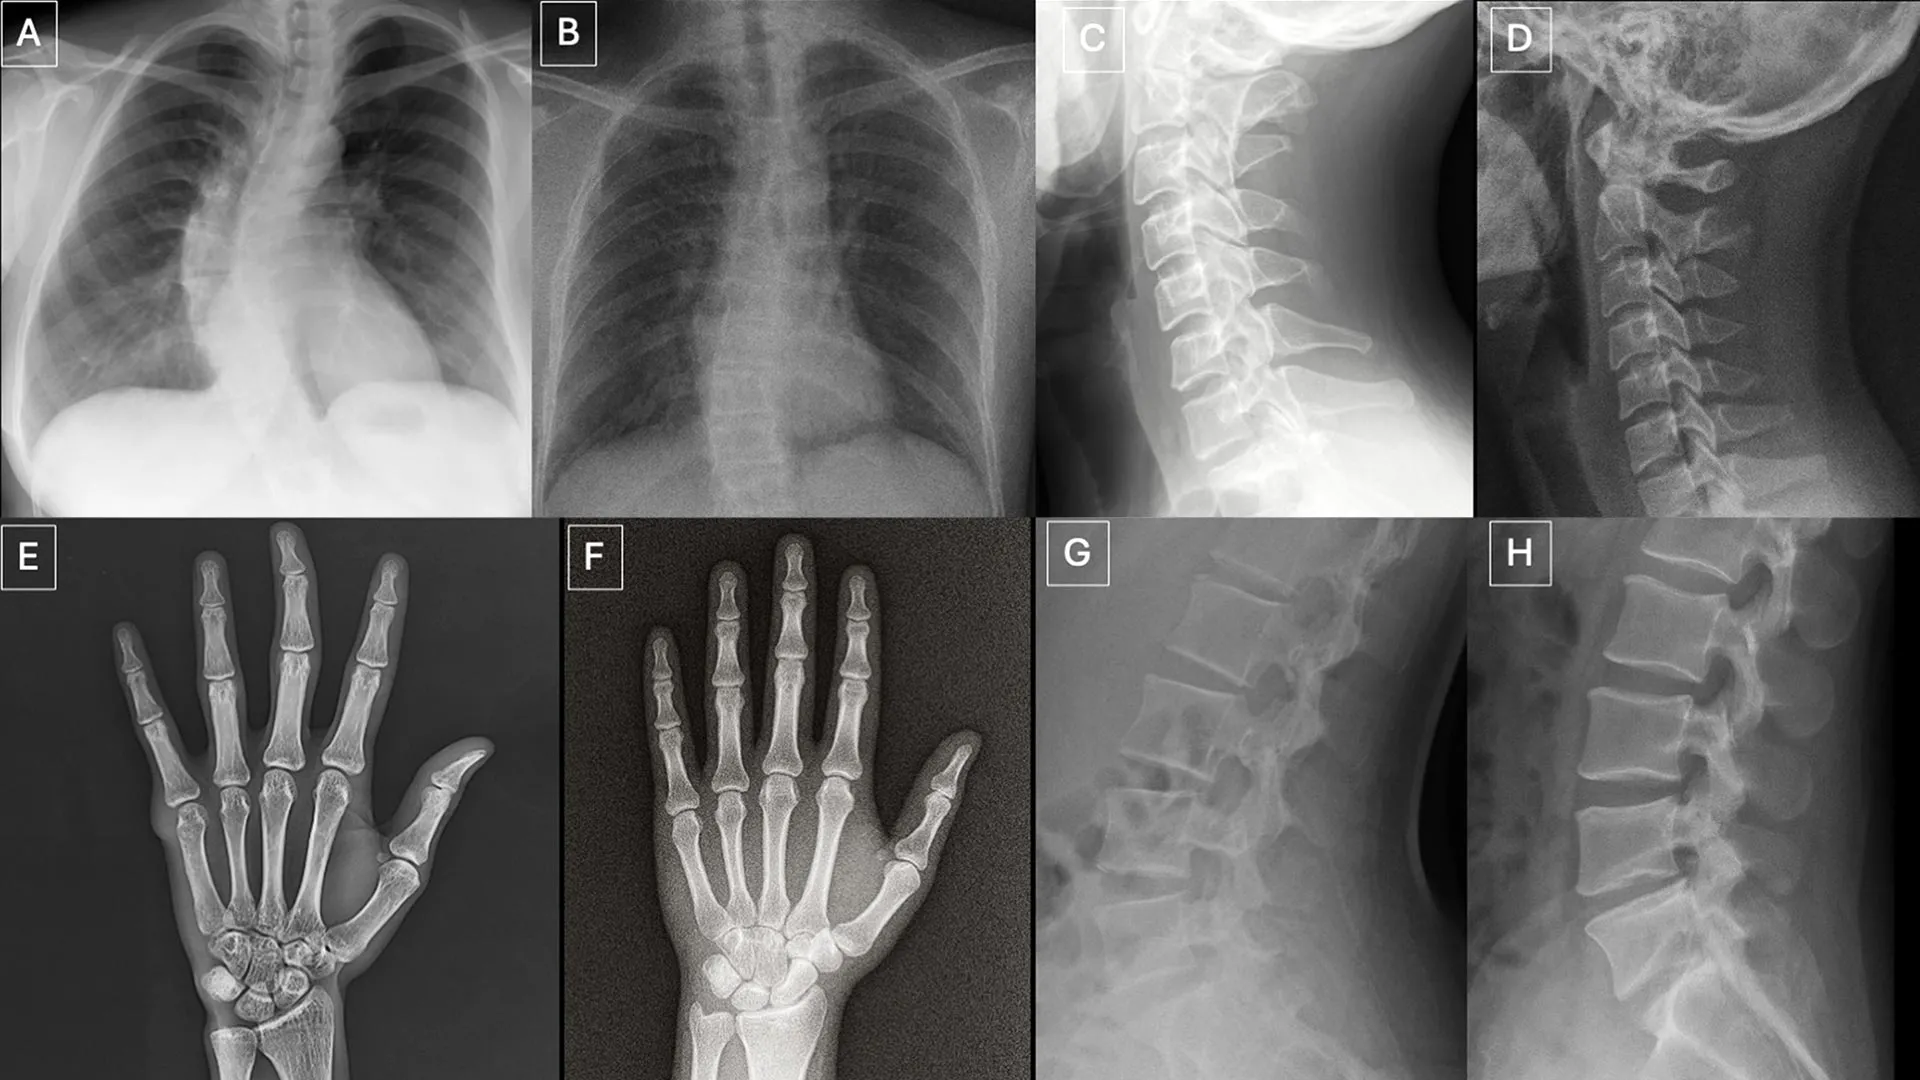

دراسة جديدة نشرت في 24 مارس في الأشعة، مجلة الجمعية الإشعاعية لأمريكا الشمالية (RSNA)، تكشف أن علماء الأشعة ونماذج اللغات الكبيرة متعددة الوسائط (LLMs) يواجهون صعوبة في التمييز بين الأشعة السينية الحقيقية والصور “المزيفة العميقة” الناتجة عن الذكاء الاصطناعي (AI). تثير النتائج مخاوف بشأن المخاطر التي تشكلها الصور الطبية الاصطناعية وتسلط الضوء على الحاجة إلى أدوات وتدريب أفضل لحماية دقة التصوير الطبي وإعداد المتخصصين في الرعاية الصحية للتعرف على الصور المزيفة.

شمل البحث 17 متخصصًا في الأشعة من 12 مؤسسة في ست دول (الولايات المتحدة، فرنسا، ألمانيا، تركيا، المملكة المتحدة، والإمارات العربية المتحدة). وتراوحت خبرتهم من المبتدئين إلى المتخصصين مع ما يصل إلى 40 عامًا من الممارسة. في المجمل، فحصت الدراسة 264 صورة للأشعة السينية، مقسمة بالتساوي بين عمليات المسح الحقيقية وتلك التي تم إنشاؤها بواسطة الذكاء الاصطناعي.

عندما لم يتم إخبار أخصائيي الأشعة بأن الصور المزيفة قد تم تضمينها، تعرف 41% فقط على الأشعة السينية الناتجة عن الذكاء الاصطناعي. وبمجرد إبلاغهم بوجود صور اصطناعية، ارتفع متوسط دقتهم في التمييز بين الصور الحقيقية والمزيفة إلى 75%.